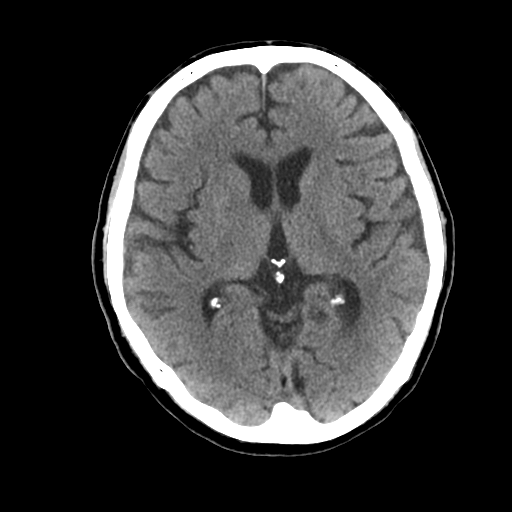

1-1. 高吸収領域の検出・表示例(下)

頭部CT検査において、周囲に比べ白く映る部分(高吸収領域)が見られる場合には、脳出血が疑われます。脳出血は高血圧・脳腫瘍・脳血管の異常などが要因となり、脳の動脈が破れて脳内部に出血した状態を指します。一方、周囲に比べ黒く映る部分(低吸収領域)が見られる場合には、脳梗塞が疑われます。脳梗塞は、脳内の血管が詰まるなどにより血液の流入が止まり、脳に酸素や栄養が行き渡らなくなる状態です。また、急性期の脳梗塞では、頭部CT検査において、灰白質と白質の境界が消失するなどの所見(ECS=early CT sign)が見られ(2)、こうした所見を見落とさずに治療につなげることが肝要です。